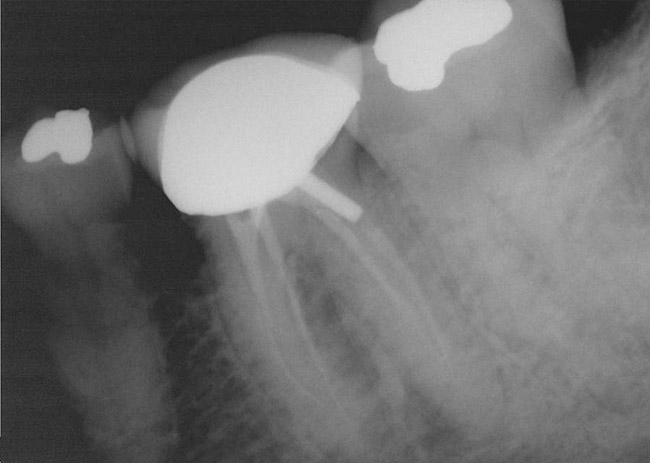

Figure 1  Tooth No. 19 had root canal therapy 8 months before this radiograph. A post was placed in the distobuccal canal. Root canals appeared instrumented and filled several millimeters short of the radiographic apex.

Figure 1

A 40-year-old man presented with a chief complaint of occasional chewing discomfort in a tooth with a history of endodontic therapy (Figure 1). The patient recounted a 1-hour visit with his dentist for the root canal therapy and subsequent visits to fabricate the crown. Eight months after the initial root canal therapy and coronal restoration, mild chewing discomfort persisted in the tooth. After discussing options and giving consent, a nonsurgical re-treatment through the new crown with intracoronal removal of the post was performed to address the patient’s chief complaint while attempting to retain the new crown (Figure 2). A 1-hour appointment was necessary to achieve these objectives (Figure 3). The patient’s symptoms disappeared and the access preparation was subsequently restored.

This case best explicates the word efficiency as it pertains to clinical endodontics. While the original root canal and the re-treatment were both performed within the same time frame, the quality, the standard of care, and, inevitably, the outcome were dissimilar in the same tooth. The first procedure was performed quickly; the second was done efficiently. This brings up the question of skill and experience as functions of efficiency in clinical procedures.